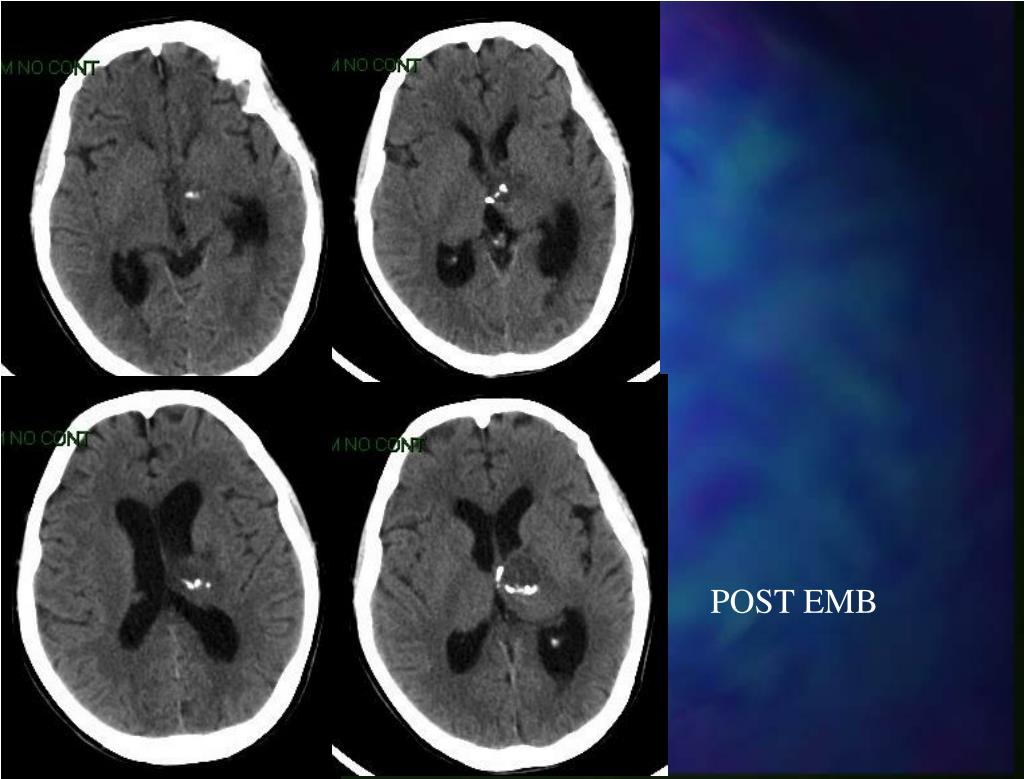

22. POST EMB

23. POST EMB